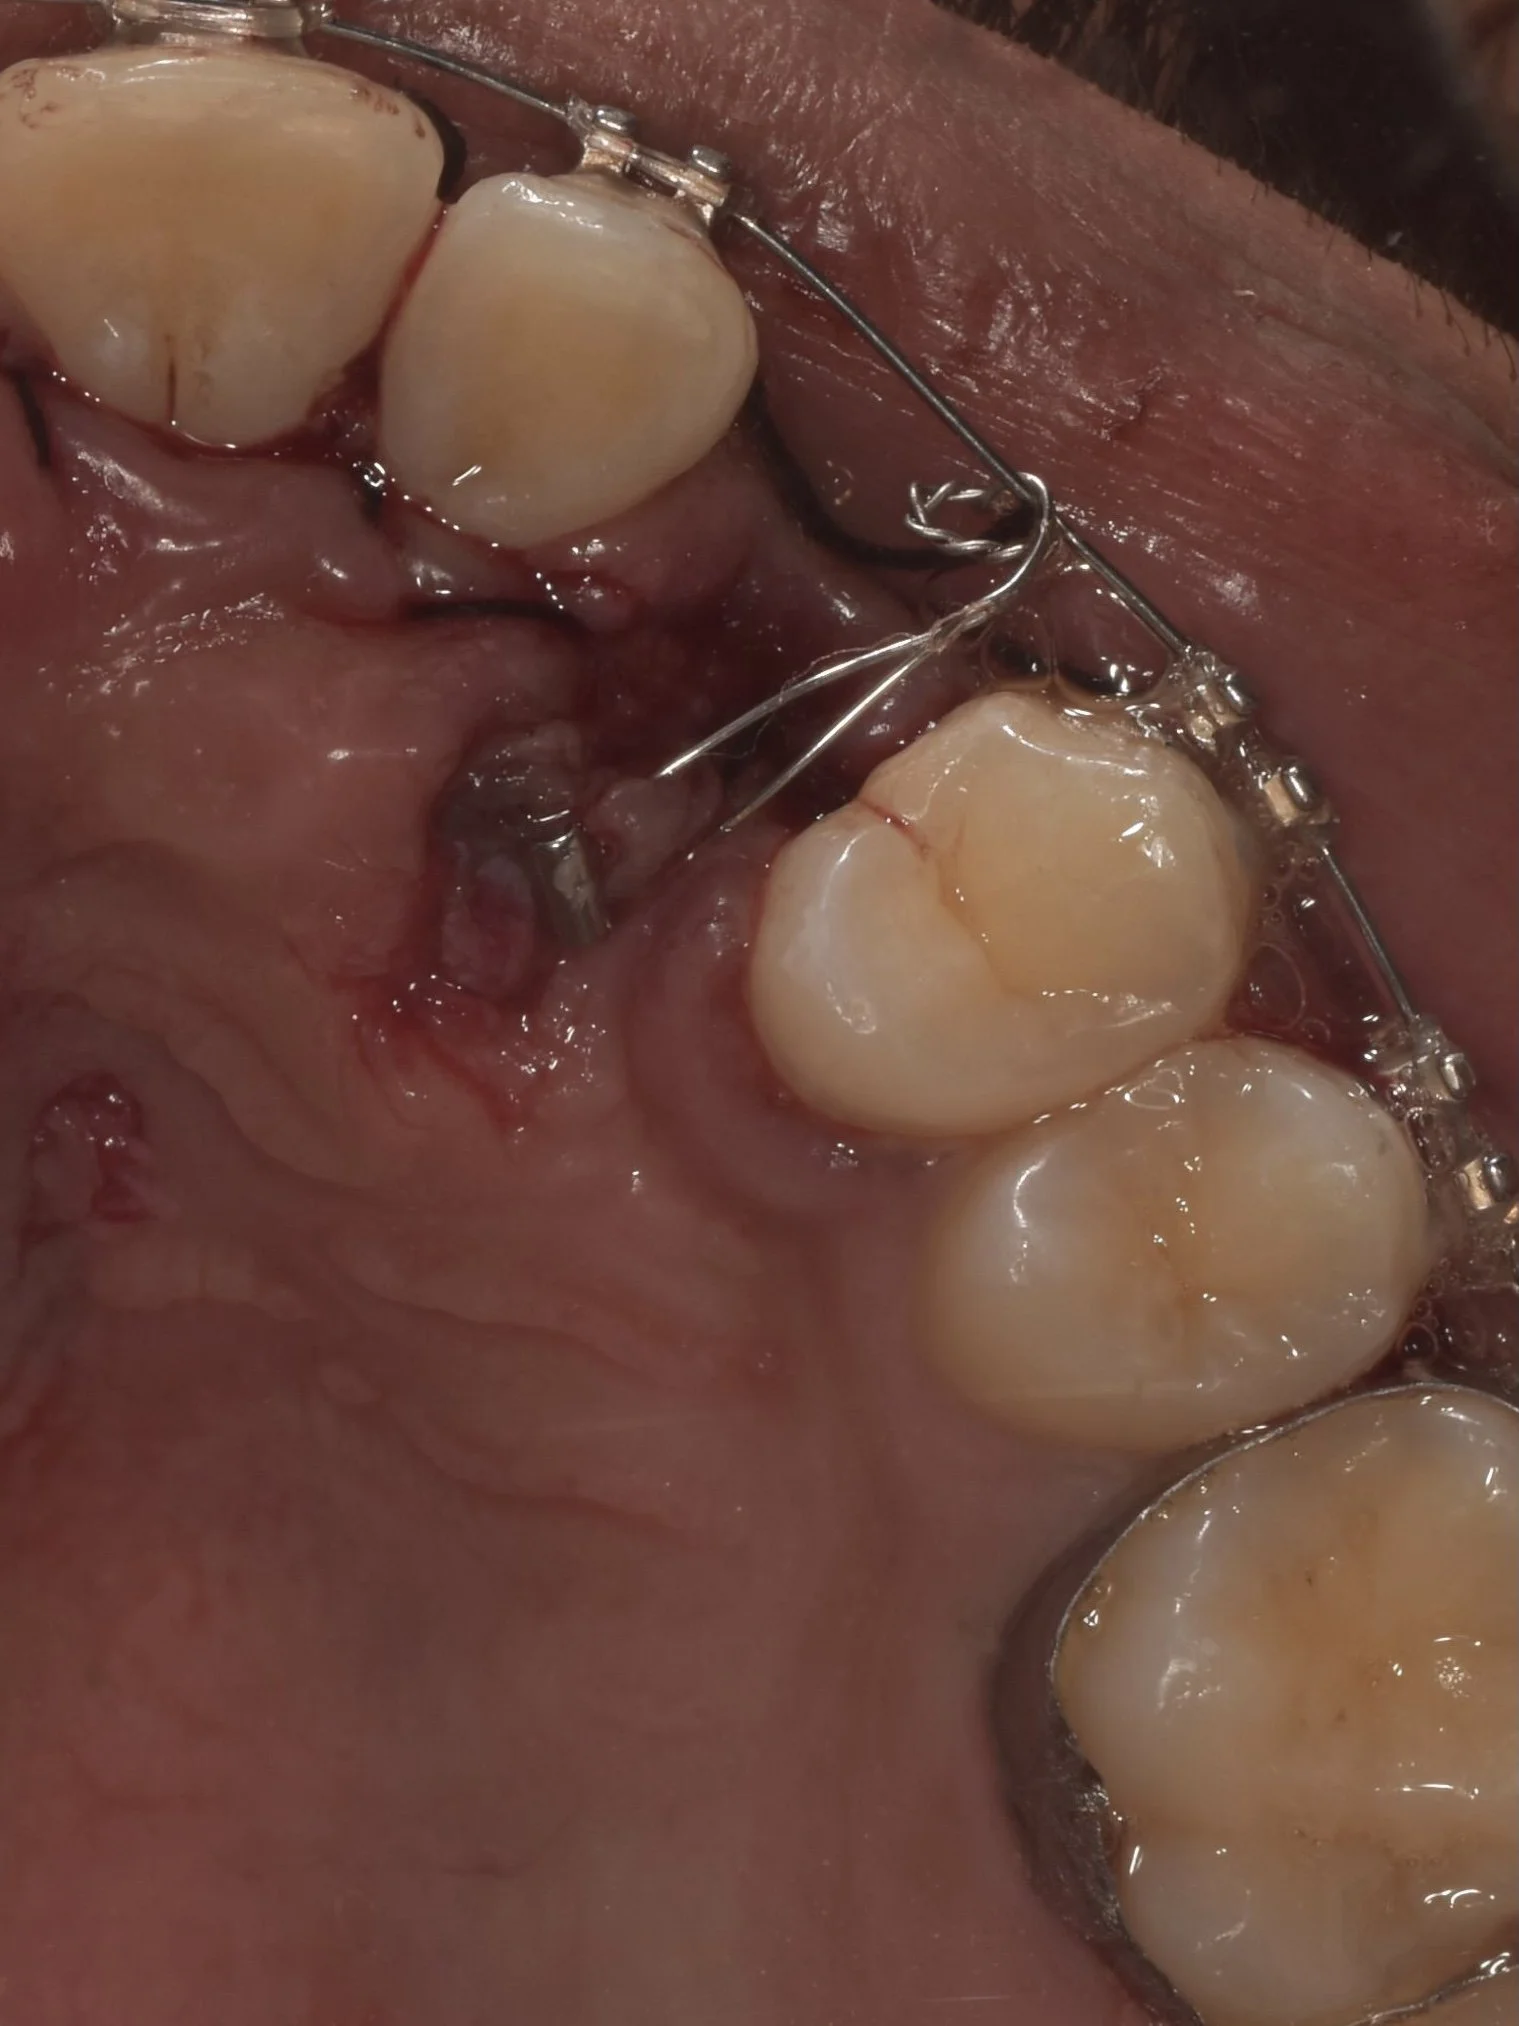

Arch expansion therapy

Craniofacial Orthopedics